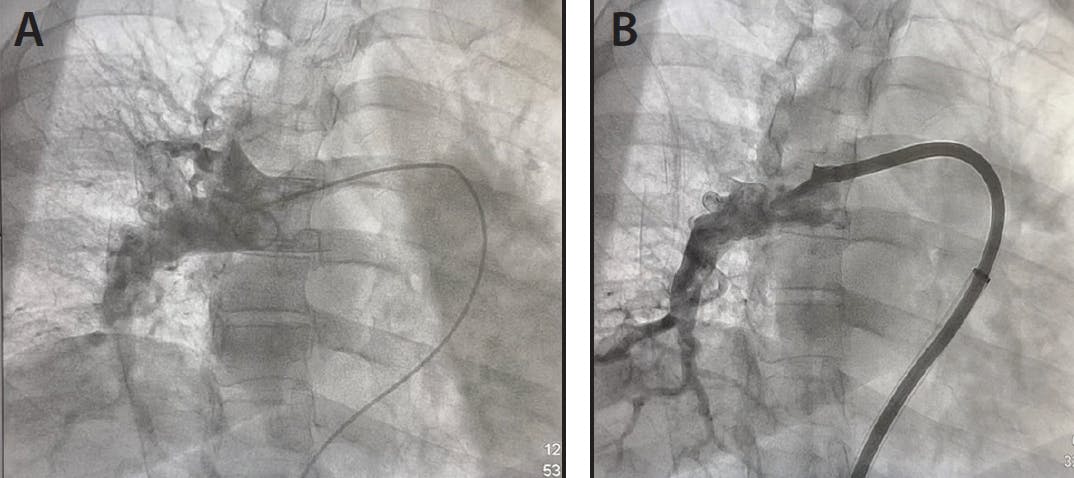

After access was gained in the groin, pressures were taken in the main PA showing a preprocedural reading of 29/9 mm Hg (mean, 16 mm Hg). Lightning Flash was then introduced into the vasculature and navigated into the main PA. With the catheter at the face of thrombus, aspiration was initiated. The Lightning Flash catheter was then torqued to engage thrombus in both the right and left PA to remove the bilateral clot burden (Figure 1). Once the thrombus was sufficiently addressed, angiograms were obtained and pressures were taken for further confirmation (Figures 2A and 2B), showing great improvement at 21/4 mm Hg (mean, 10 mm Hg).

Figure 1. Clot burden removed.

Figure 2. Preprocedural angiogram of the main PA (A) and postthrombectomy angiogram of the right PA (B).